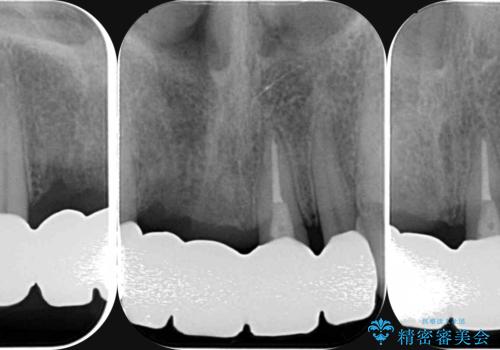

前歯が折れた 前歯部審美セラミックブリッジ治療

- ブリッジの根元が折れ、審美性の改善・治療を求めて来院されました。

保存の難しい歯を抜去しロングブリッジによる補綴を選択しました。

- 57万円(仮歯・ファイバーコア・ジルコニアクラウン×5)費用は治療当時の料金となります

かみ合わせの観点からインプラント治療は難しく、入れ歯も希望されなかったためブリッジによる補綴を選択しました。